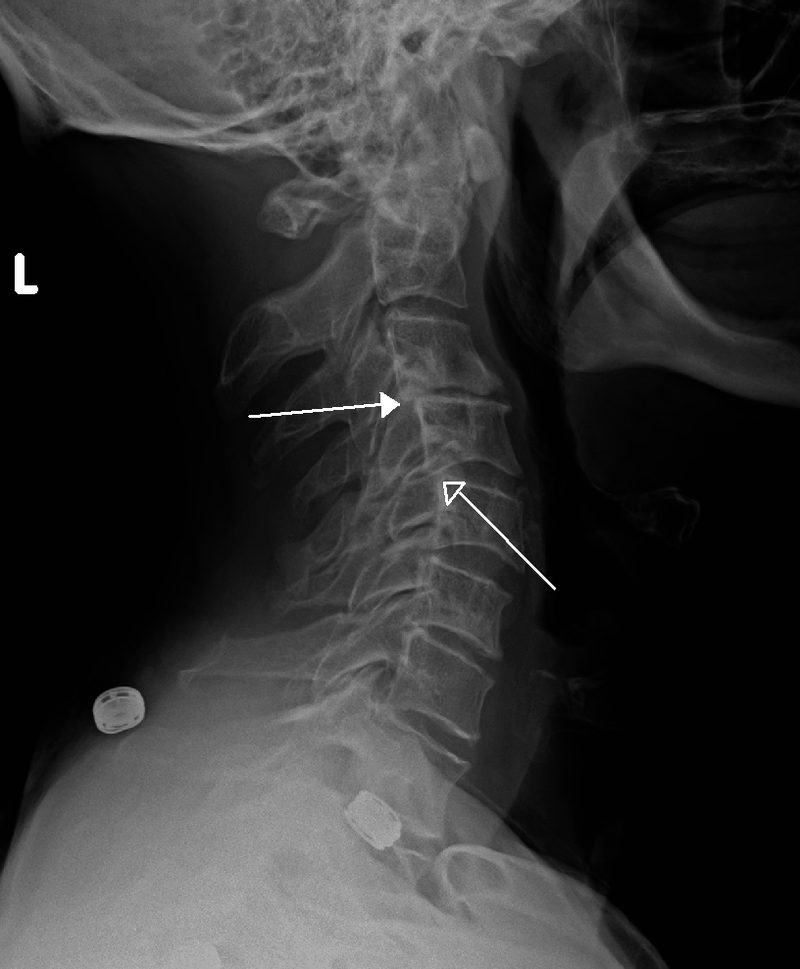

척추전방전위증의 엑스레이(x-ray) 촬영 이미지